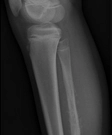

Ewing Sarcoma

Ewing Sarcoma is a rare type of cancer that occurs in bones or in the soft tissue around the bones. Most often it begins in the leg bones and in the pelvis, but it can occur in any bone